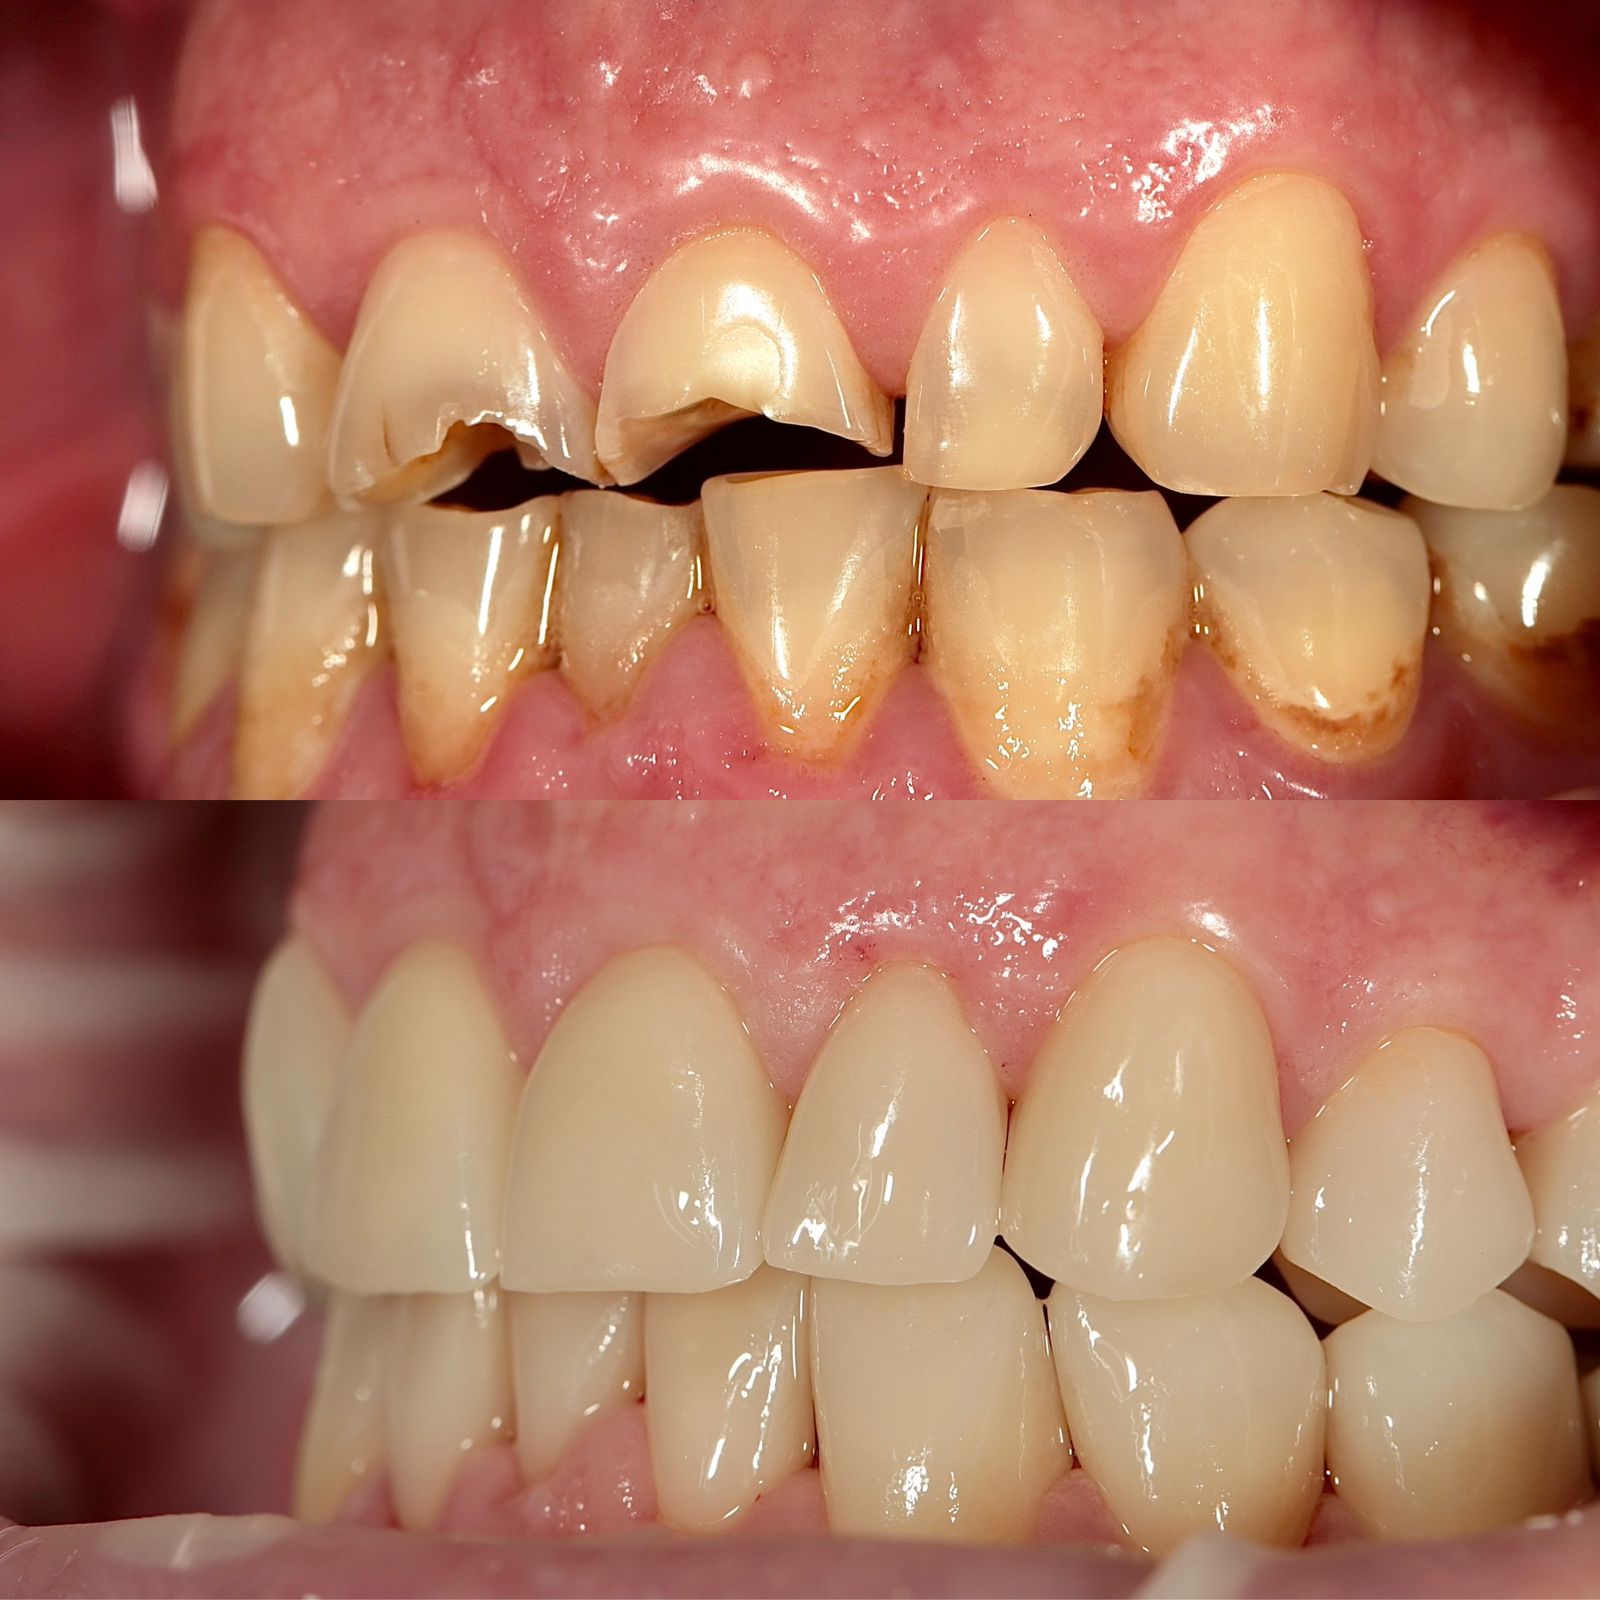

Циркониевые коронки во фронтальном отделе

Керамические виниры и коронки из оксида циркония

Патологическая стираемость, снижение прикуса . Как помочь?

- Остановить разрушительный процесс.

- Вернуть изначальный уровень высоты коронок.

- Заменить старые протезы, при необходимости.

- Адаптация к новому положению челюсти и ее работе.